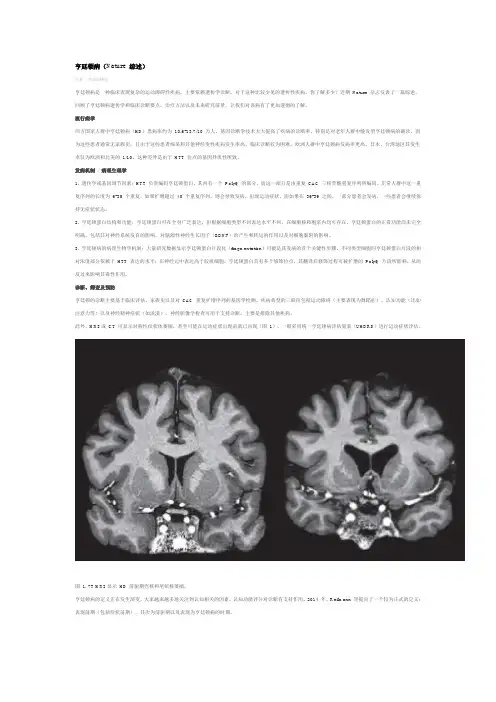

影像学检查发现有尾状核萎缩,额角扩大,部分伴有皮质萎缩,基因检测是该病重要的诊断方式。

为探讨HD 的临床特点,本文对1例临床表现疑似HD患者进行影像学及基因的CAG重复序列的检查,证实了临床推断。